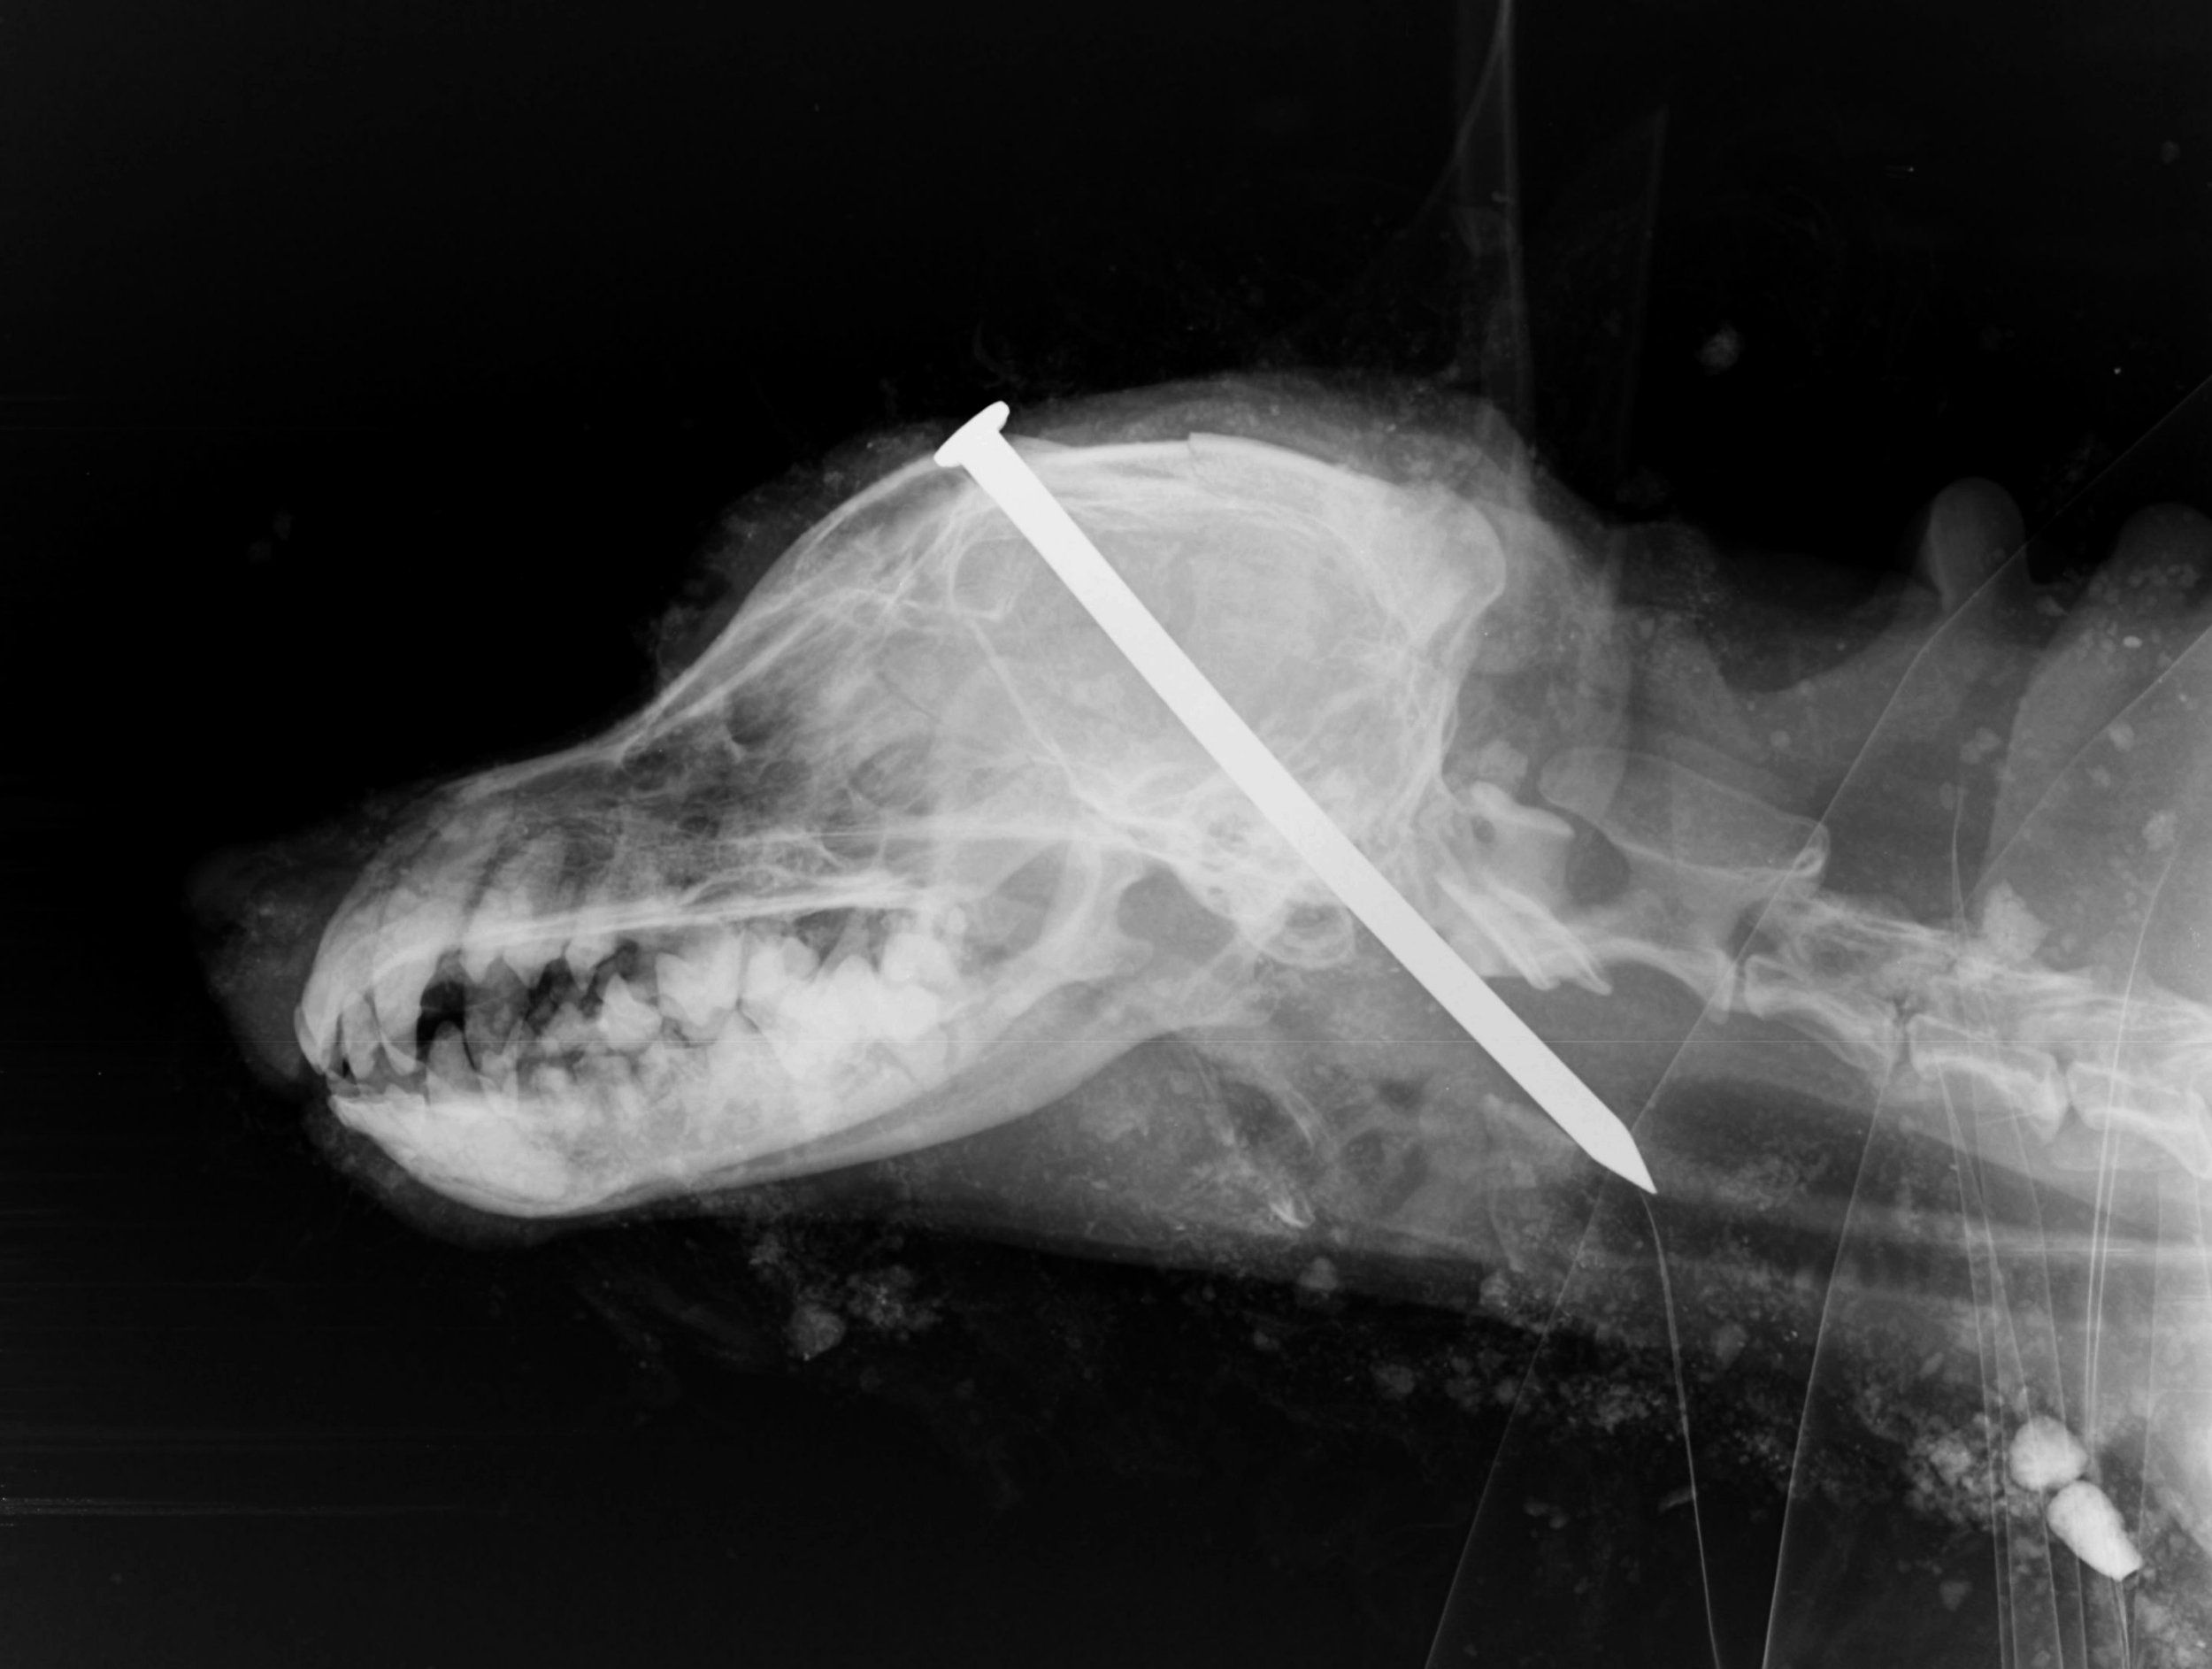

Un barbat a gasit un caine cu un cui batut in craniu, ingropat de viu, in Anglia. Cand l-a descoperit, animalul era in viata.

Barbatul l-a dezgropat si l-a dus la veterinar, insa bietul patruped nu a mai putut fi salvat, asa ca medicii au decis sa il eutanasieze.

Cei de la Protectia Animalelor au facut publice mai multe poze grafice cu animalul pentru a incerca sa-i prinda pe vinovatii acestui atac terifiant.